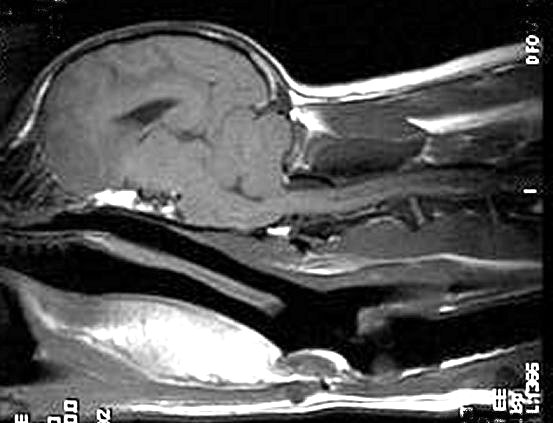

3 years old

No symptoms of SM

Mild hydrocephalus

Moderate Malformation, cerebellum

moderately squashed

Very slight herniation of cerebellum

Medulla squashed/kinked

No syrinxes